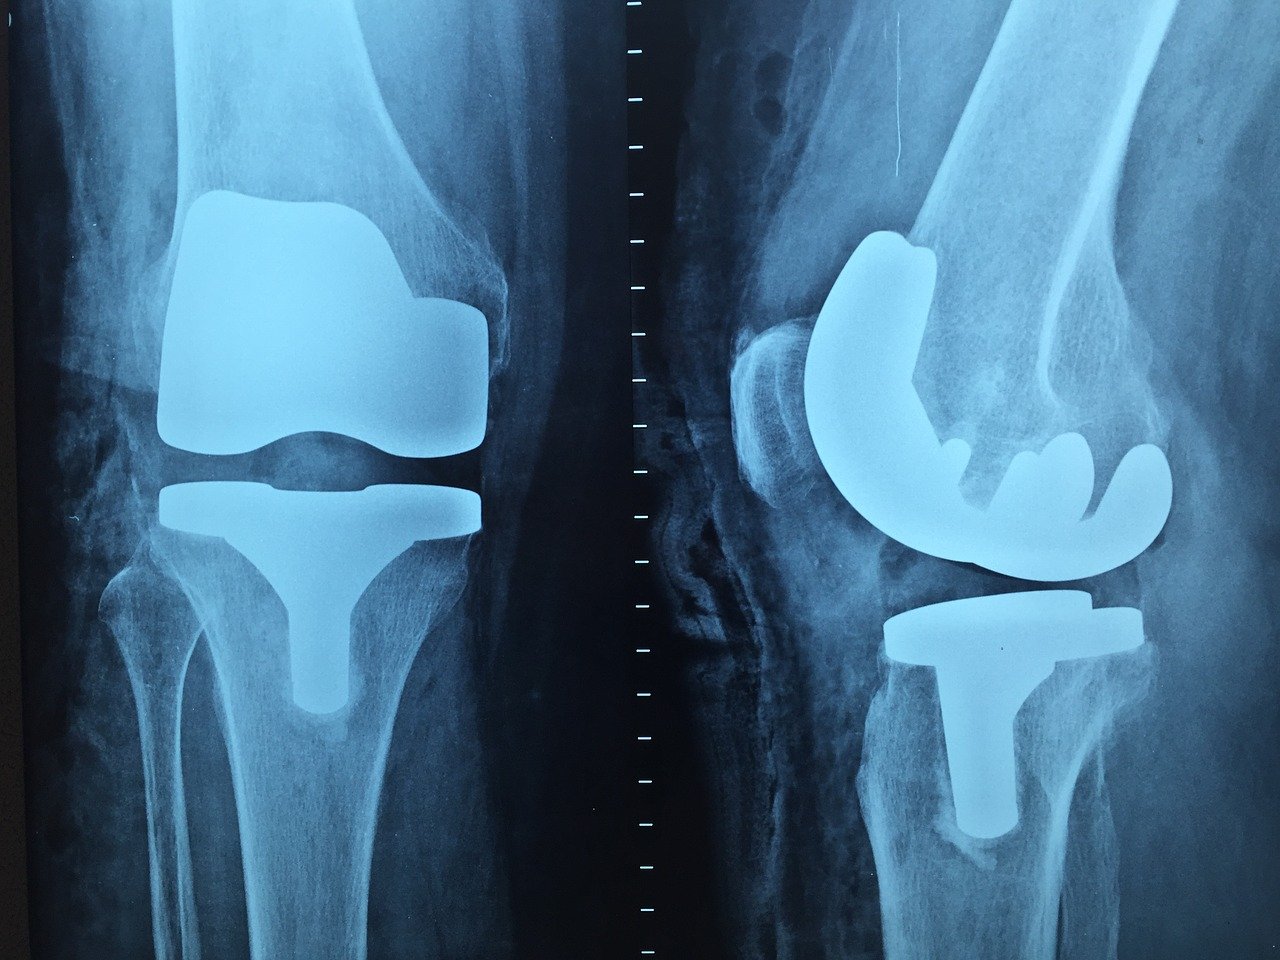

From www.atxortho.com

Patient's Guide to Total Knee Replacement ATX Orthopedics Different Types Of Orthopedic Surgery Learn about orthopedic surgeons, who treat musculoskeletal conditions with surgery and nonsurgical therapies. Here are some of the most common orthopedic procedures in the u.s. Common types of shoulder surgeries include rotator cuff repair, total shoulder replacement, and arthroscopy (e.g., for frozen. Mayo clinic orthopedic surgeons have experience treating all types of musculoskeletal conditions. 8 types of shoulder surgeries. Bone. Different Types Of Orthopedic Surgery.